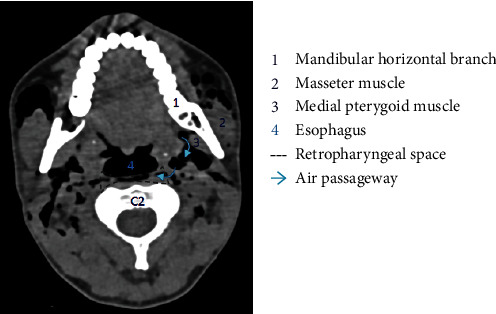

Regarding the physiopathology of subcutaneous emphysema, different superficial and deep fascias delimit spaces in the cervicofacial region. These spaces will communicate with each other, allowing the propagation of air [10]. At the mandibular level, the roots of the third molars are in contact with the submandibular space [11, 13, 14] and separated from the sublingual space by the mylohyoid muscle. We observed the presence of air in the submaxillary space in our patient (Figure 5). This air can progress from the submaxillary space to the parapharyngeal space, and then to the retropharyngeal space (Figures 6 and 7). This occurred in our patient. The retropharyngeal space communicates with the mediastinum [2, 10–12, 15–17], thus allowing air to continue to spread and cause pneumomediastinum, which was also observed in the present report (Figure 8). The incidence of air distribution in the 26 cases reported in the literature is presented in Table 3, with pneumomediastinum recorded in 20 patients (77% of cases).

Computed tomography scan of the axial section through C2 of our patient. Air diffused from the submandibular space to the parapharyngeal space, and then to the retropharyngeal space.

Figure 7.

Schematic of the axial section through C2. Air can diffuse from the submandibular space to the parapharyngeal space, and then to the retropharyngeal space. IX: glossopharyngeal nerve; X: vagus nerve; XI: accessory nerve; XII: hypoglossal nerve.